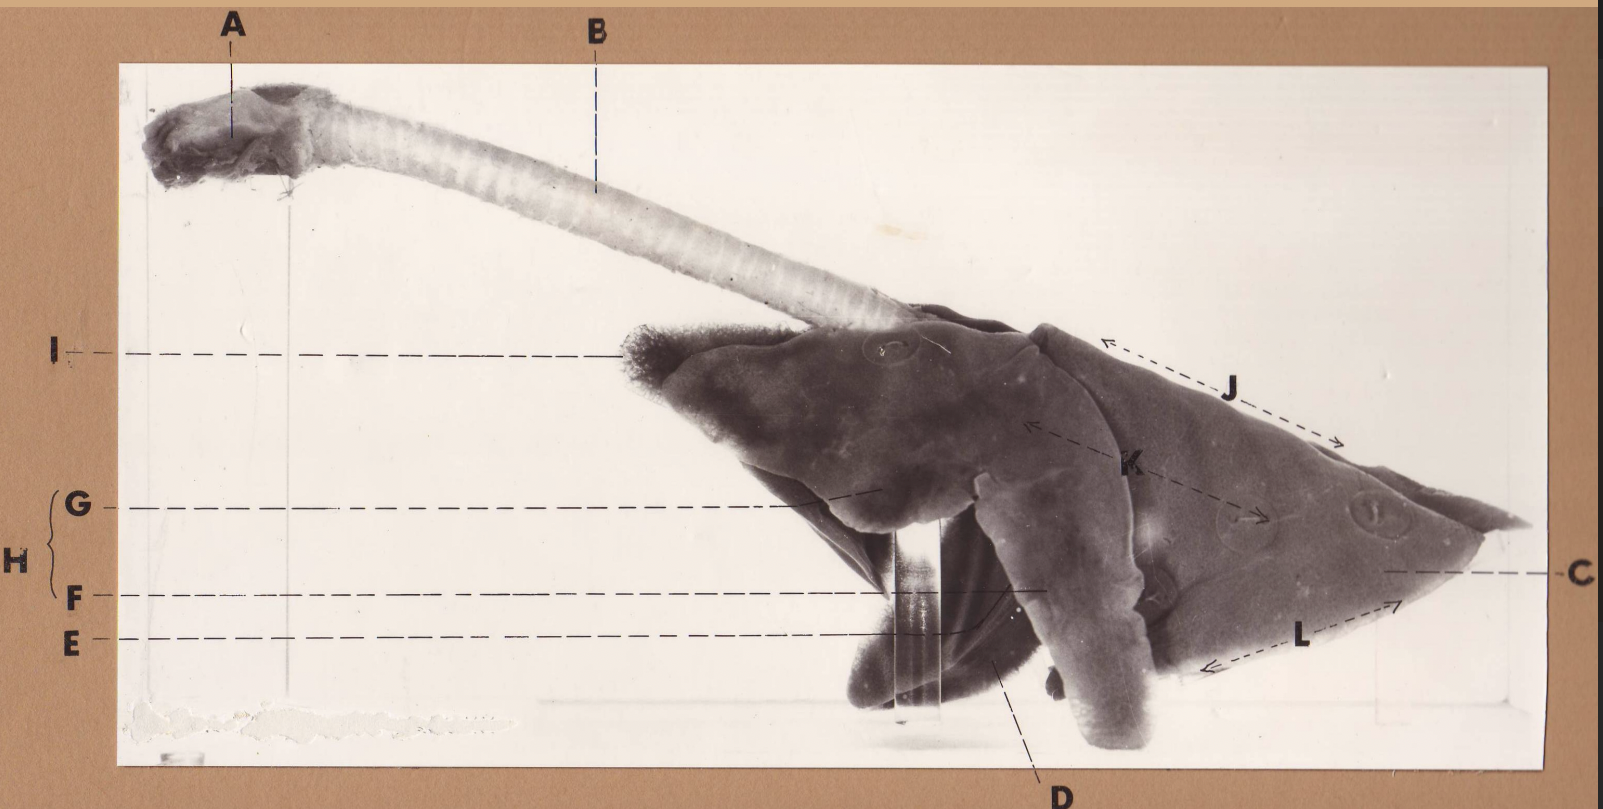

A

(cat larynx/trachea/lungs, L lateral)

larynx

B

(cat larynx/trachea/lungs, L lateral)

trachea

C

(cat larynx/trachea/lungs, L lateral)

caudal lobe

D

(cat larynx/trachea/lungs, L lateral)

middle lobe

E

(cat larynx/trachea/lungs, L lateral)

cardiac notch

F

(cat larynx/trachea/lungs, L lateral)

caudal segment, cranial lobe

G

(cat larynx/trachea/lungs, L lateral)

cranial segment, cranial lobe

H

(cat larynx/trachea/lungs, L lateral)

cranial lobe

I

(cat larynx/trachea/lungs, L lateral)

apex

J

(cat larynx/trachea/lungs, L lateral)

dorsal border

K

(cat larynx/trachea/lungs, L lateral)

costal surface

L

(cat larynx/trachea/lungs, L lateral)

basal border